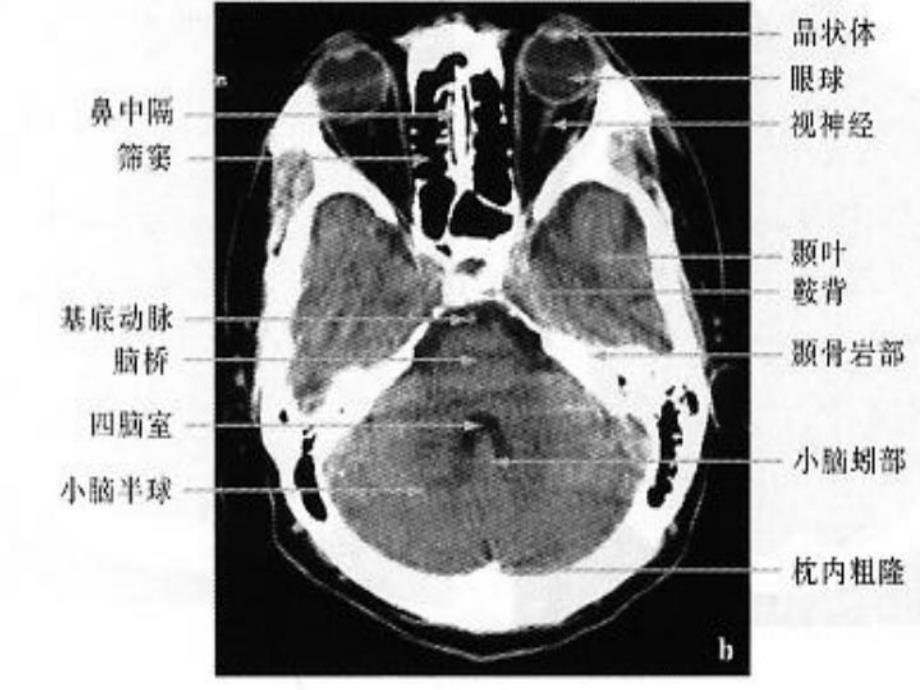

颅脑、解剖 硬膜外血肿 硬膜下血肿 蛛网膜下腔出血 脑挫裂伤 脑积水(交通性、阻塞性)(正压、负压)(占位效应)